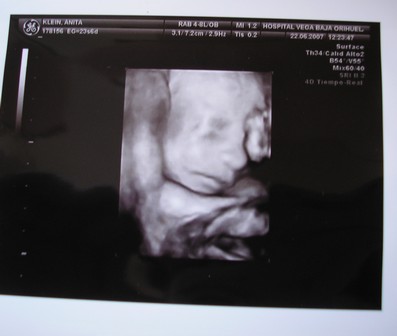

Ma kora reggel megszülettek a kicsi fiúk, róluk hoztam képeket nektek. Éjfél körül szivárgott a huginál a magzatvíz, felhívták a kórházat, ott mondták, inkább menjenek be, az a biztos. Kapott antibiotikumokat, de sajnos beindult a szülés. 4.32-kor megszületett a Bálint, 1990gr és 44cm, valmint 4.39-kor a Kristóf 2170gr és 44cm. Valami tüdősegítő oxigént kapnak, a Bálintnak sűrű volt a vére, de úgy néz ki, hogy helyre áll magától. Amint megindul a teje kiveheti őket szoptatni, talán 1 hetet kell bent lenni.

Kép

Ő a Kristóf.

Ő pedig a Bálint.

Holnap találkozok vele, majd még mesélek.